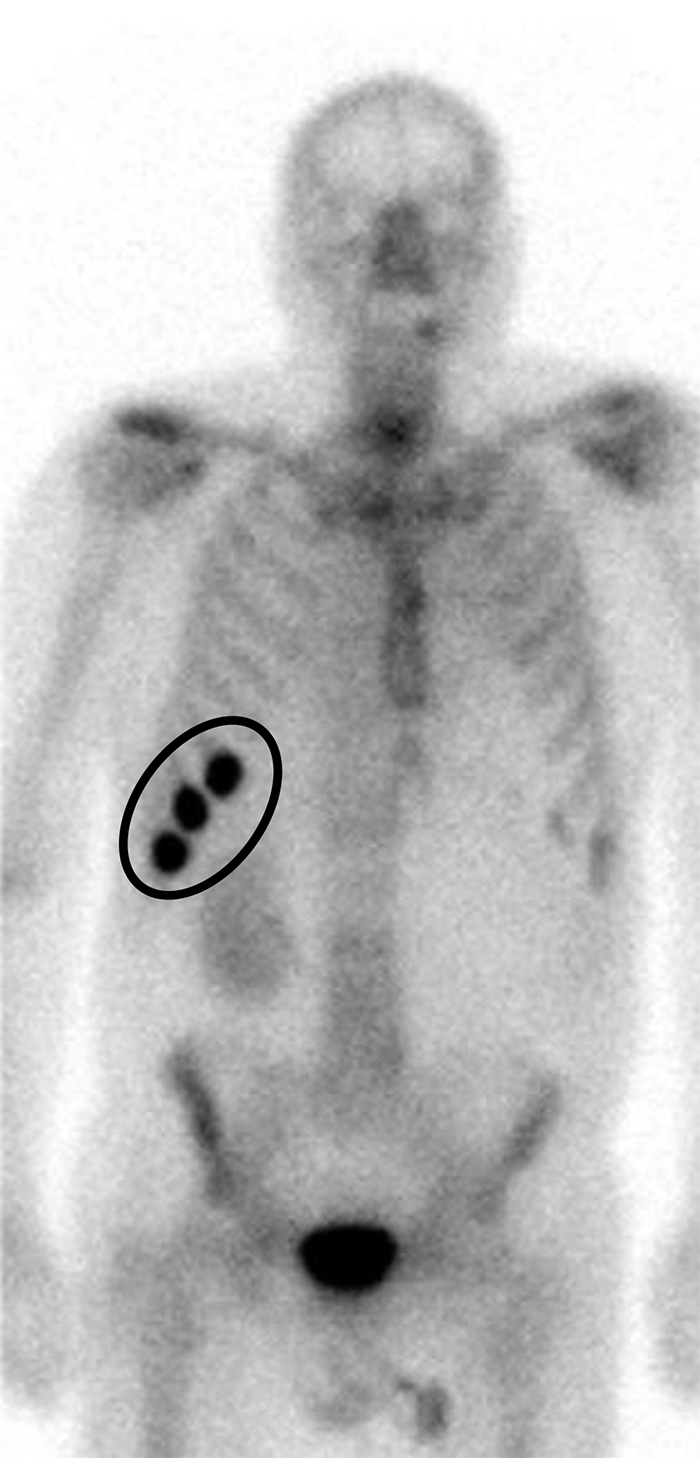

Fratture costali.

La scintigrafia ossea whole-body in proiezione anteriore con 99mTc-MDP mostra ipercaptazione multifocale con distribuzione lineare a carico delle coste anteriori di destra. Questo allineamento verticale “a rosario” è il classico segno di un evento traumatico o microtraumatico che ha coinvolto più coste adiacenti. Un pattern lineare suggerisce trauma (benigno). Un pattern non lineare o sparso (random) è sospetto per metastasi e richiede approfondimento morfologico (TC). Una captazione focale (puntiforme) è generalmente benigna. Una captazione longitudinale (che si estende lungo l’asse della costa) è altamente sospetta per lesione maligna. Il riscontro di un’unica lesione costale isolata, senza altre aree di ipercaptazione nel resto dello scheletro, ha una bassa probabilità (~10%) di essere di natura metastatica.